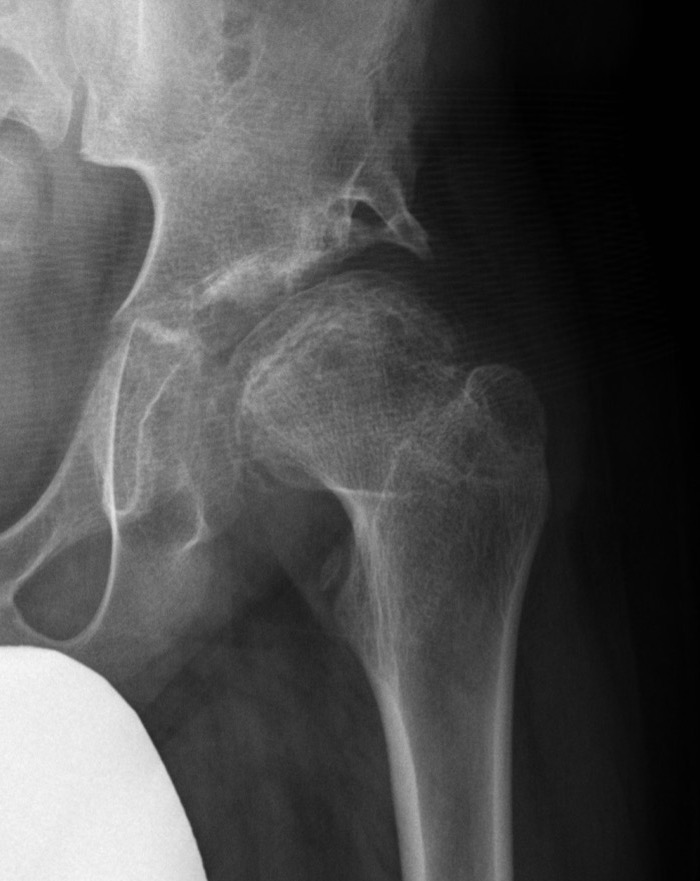

Uncontained hip / lateral extrusion

Femoral Varus Osteotomy (FVO)

Indications

Herring grade B or B/C

> 8 years at age on onset

Full containment of cartilaginous head

No hinge abduction